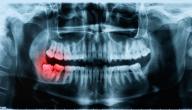

ضرس العقل

هو آخر أسنان الإنسان ظهوراً؛ حيث يظهر بعد أن يبلغ الإنسان، وقد سمّي بضرس العقل لأنّه يظهر للإنسان عند الوصول لسنّ الرشد، بينما أثبت علميّاً أنّه لا علاقة له بالعقل ونموّه، وهو ثالث ضرس للإنسان، وقد يصل عدد أسنان العقل إلى أربعة، كلّ واحد منها في فك وجهة.

- اختفاء ضرس العقل وعدم ظهوره، ويرجع السبب لاختفاء برعم السن من الأساس، أو لصغر حجم الفك لدرجة لا تسمح بظهور أيّة أسنان إضافيّة، أو قد ينمو ضرس العقل بشكل مائل أو عرضي، ممّا يبقيه تحت اللثة، ولا يظهر بين الأسنان.

إنّ ظهور ضرس العقل بشكل كامل أو مائل أو عرضي يسبّب التعب والإعياء، والألم، وارتفاع في درجة الحرارة، وانتفاخ في اللثة، وصعوبة في بلع الطعام أو فتح الفم بشكل كامل، ويعود ذلك لالتهاب اللثة، وتكوّن الإفرازات الصديديّة، ونتيجة الضغط المستمر على الأعصاب قد ينتقل الألم للأذن والعين ولأسنان الفك كاملةً، وقد يسبّب تسوّس الأسنان المجاورة، وهذه الأعراض والمشاكل قد تظهر وقد لا تظهر، ومن الممكن أن يظهر معظمها اعتماداً على الحالة.